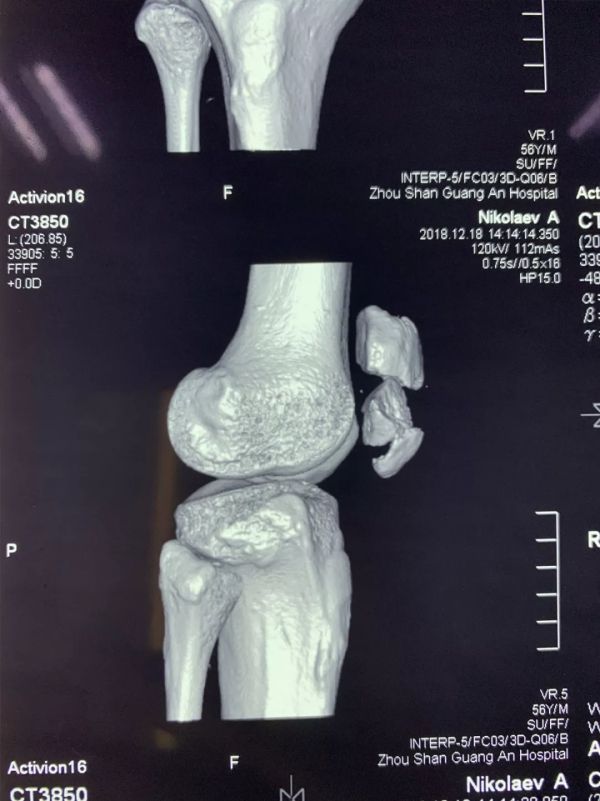

近日,廣安醫(yī)院關(guān)節(jié)科羅軍主任帶領(lǐng)科室團(tuán)隊(duì)成員為一名來自俄羅斯的患者成功施行了右髕骨粉碎性骨折切復(fù)內(nèi)固定手術(shù)治療,術(shù)后三天患者能自行起床活動(dòng)。

患者從遙遠(yuǎn)的俄羅斯來到美麗的舟山群島船廠指導(dǎo)工作,旅途中不慎跌倒,導(dǎo)致右髕骨粉碎性骨折,需行手術(shù)治療,患者來到廣安醫(yī)院就診,然而語言不通,患者只能聽懂簡(jiǎn)單的英文,怎么辦?機(jī)智的易觀俊主治醫(yī)師用手機(jī)上的翻譯軟件,搭好了醫(yī)患溝通的橋梁。